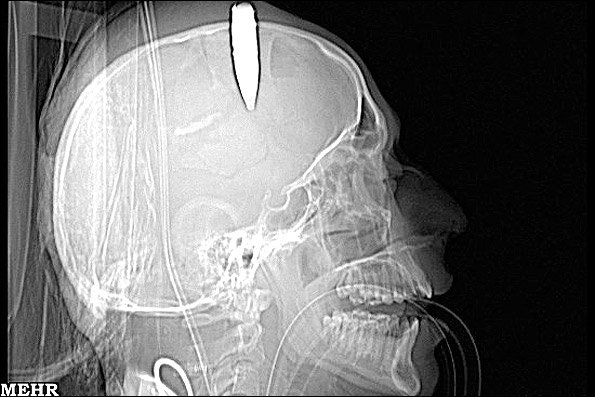

در فوریه 2011 یک شهروند چینی به نام "نی" که حداقل به مدت 4 سال از سردردهای مزمن شدید و عجیبی رنج می برد سرانجام به بیمارستان مراجعه کرد.

پزشکان پس از تصویربرداری رادیوگرافی در جمجمه این مرد یک تیغه 10 سانتیمتری چاقو کشف کردند. پس از اعلام نتایج آزمایشات، این مرد چینی به یادآورد که دقیقاً چهار سال قبل با یک دزد درگیری منجر به ضرب و جرح داشته است.

وی در این خصوص گفت: "با گذشت زمان سردردهایم آنقدر شدید شده بود که برای تسکیل درد سر و گوشهایم باید آمپولهای مسکن قوی تزریق می کردم."